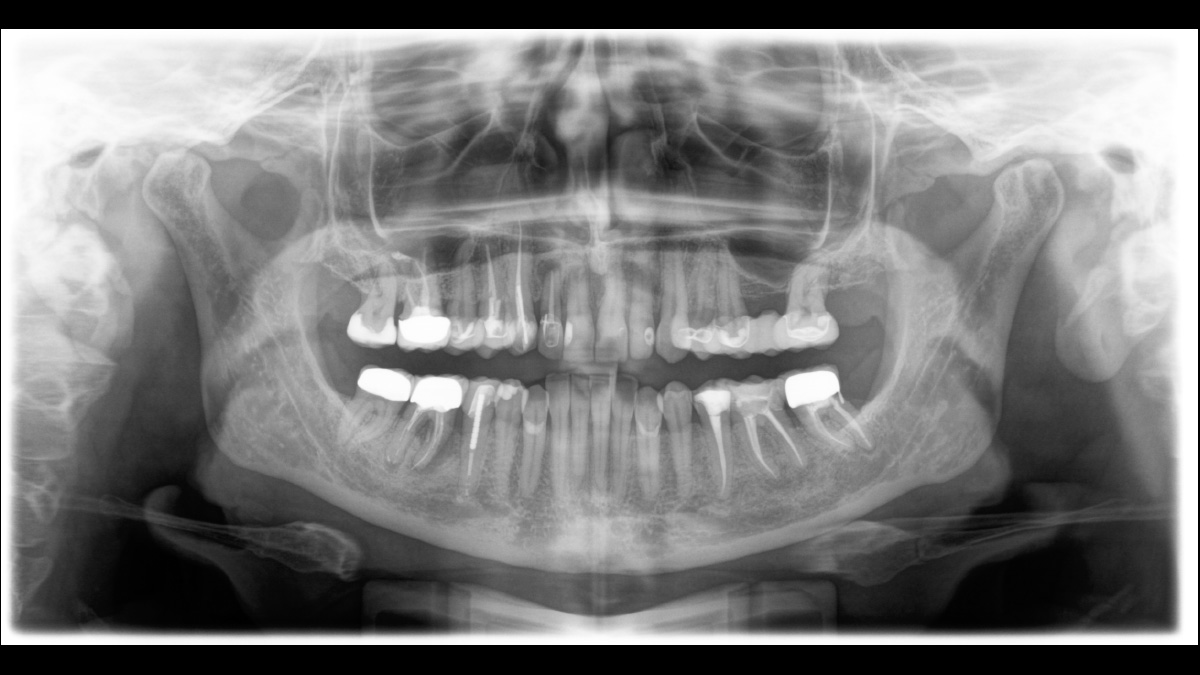

El equipo de radiología 2D/3D de alta calidad con una amplia gama de servicios para cada clínica. Ya sea como un dispositivo puramente 2D o como un módulo 3D, el Orthophos S es un socio confiable y está optimizado para las tareas diarias. Su sensor CsI Plus con función de autofoco garantiza imágenes claras, incluso en casos anatómicamente difíciles. El posicionamiento automático del paciente junto con el bloque de mordida oclusal patentado permite un posicionamiento del paciente fácil y que ahorra tiempo. Para su uso en ortodoncia, la Orthophos S también está disponible con un brazo cefalométrico opcional. Y como para Dentsply Sirona es importante estar preparado para el futuro, el brazo cefalométrico se puede reacondicionar en cualquier momento.

Para la mayoría de las clínicas, se utiliza un equipo de radiología con dos objetivos principales en mente: capturar la mejor imagen posible para respaldar un diagnóstico preciso y exacto, y garantizar que el paciente se sienta cómodo durante el proceso. El Orthophos S ofrece soluciones únicas y patentadas para apoyar ambos objetivos con:

El enfoque correcto es crucial para excelentes radiografías panorámicas. Con la función de autofoco, usted recibirá automáticamente una imagen con la mejor nitidez posible en foco. Los dispositivos de radiología de Dentsply Sirona toman varios miles de imágenes individuales en un ciclo e identifican automáticamente las áreas donde la mandíbula está posicionada de manera óptima. Luego, sin ningún paso manual adicional, estas imágenes se muestran en una nítida imagen final.